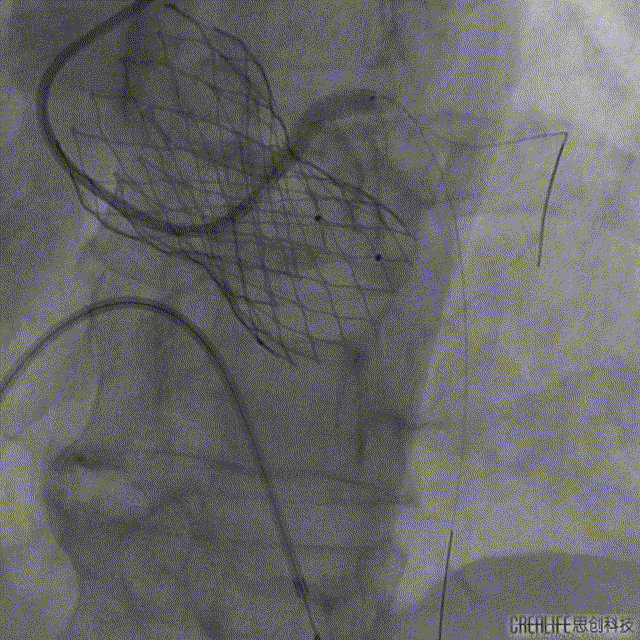

左主干开口被瓣膜阻挡

最后造影